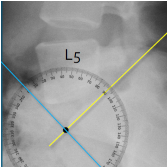

Q what is the name of this measurement? and what is the average + range?

A: Lumbosacral Angle

assesses the angle of the sacrum relative to a horizontal line. The average is 41°, with a range of 26-57°.